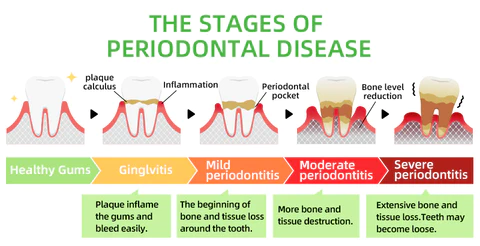

Every day, food residues in our mouths create a breeding ground for various bacteria and microorganisms within the oral cavity. This can result in a range of oral health issues, including bad breath, mouth ulcers, yellow teeth, cavities, calculus buildup, gum inflammation, bleeding gums, tooth sensitivity, weakened or missing teeth, swollen gums, toothaches, loose teeth, tooth loss, and even the risk of oral cancer.

As these conditions worsen, you may experience persistent bad breath, gum inflammation, and other problems. Bacteria continue to harm your gums, leading to issues like bleeding, pain, and redness. Without timely intervention, these oral problems can escalate, potentially causing periodontitis, dental plaque, dental calculus, loose teeth, tooth pain, and eventually tooth loss.

Remove Calculus

Calculus is calcified dental plaque that inflames the gums, which can lead to bone loss, loose teeth, tooth sensitivity, etc. FURZERO™ Herbal Brightening Oral Repair Foam can help eliminate dental plaque and remove stubborn calculus attached to teeth, making your teeth white and healthy again.